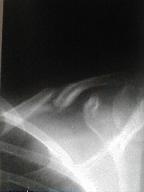

12年1月5日受傷時中枢骨片は上方転位

末梢骨片は前内下方転移

横骨折、短縮転位 |